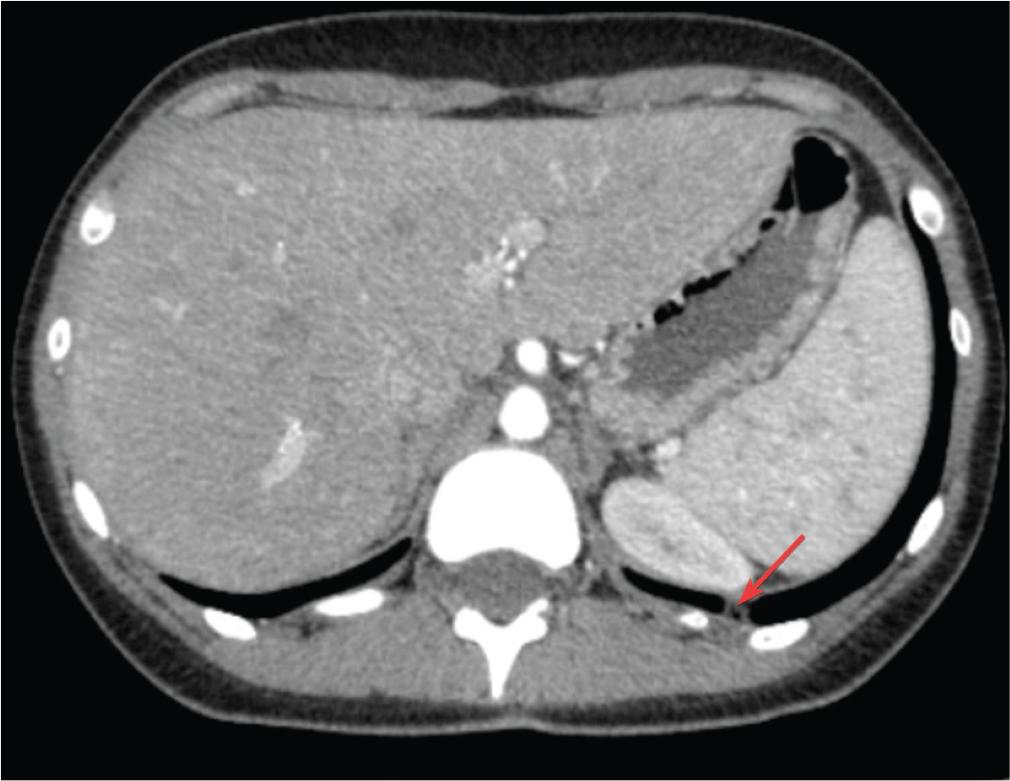

Patient A, a 22-year-old non-smoker with a 5-month history of COC use for dysmenorrhoea, presented with dyspnoea and palpitations with an acute onset 48 hr after physical exertion. The clinical examination revealed tachypnoea, peripheral oxygen saturation (SpO2) of 90%–91%, mild tachycardia (112 bpm) and arterial hypotension (90/60 mmHg). Given the clinical presentation and according to the revised Geneva score, the patient exhibited an intermediate clinical probability of PE (4). Blood tests indicated a low haemoglobin value of 9.9 g/dL, evidence of an inflammatory syndrome (C-reactive protein (CRP) = 58.11 mg/L) and elevated D-dimers (700 ng/mL). The electrocardiogram (ECG) revealed an incomplete right bundle branch block, and echocardiography showed moderate tricuspid regurgitation, moderate pulmonary hypertension (PH) with an estimated systolic pulmonary arterial pressure (sPAP) of 44 mmHg. Computed tomography (CT) confirmed the presence of a massive occlusive PE in the main pulmonary arteries and the ‘saddle’ of the pulmonary trunk, along with pulmonary infarctions in the lower lobes (Figures 1 and 2). Based on these findings and the clinical presentation, the patient was diagnosed with high-risk PE (4). Considering the haemodynamic status and the recent onset of symptoms (within 48 hr), the patient was admitted to the intensive care unit. She received systemic thrombolytic therapy (Alteplase), intravenous (IV) anticoagulation with an initial bolus of unfractionated heparin (UFH) 5000 IU followed by continuous infusion of 1200 IU/hr, as well as supplemental oxygen therapy. After 3 days, the patient’s condition significantly improved, allowing for transfer to the clinical pneumology ward, where anticoagulant therapy was continued with enoxaparin 0.6 mL s.c. every 12 hr for 7 days. The clinical evolution was favourable. Upon discharge, oral anticoagulation with apixaban was initiated at a dose of 10 mg every 12 hr for 7 days, followed by 5 mg every 12 hr, in accordance with international guidelines (5). Given the patient’s young age and the recent diagnosis of PE, suspicion of a possible thrombophilia was raised, and COC therapy was discontinued. The haematological consultation revealed a type III protein S deficiency and heterozygous Methylenetetrahydrofolate reductase (MTHFR) mutation. The patient stopped anticoagulant treatment after 6 months.

Contrast enhanced chest CT scan: pulmonary infarctions. CT, computed tomography.